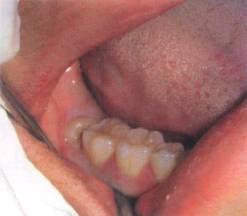

主要包括牙槽外科手术(含各种牙齿的拔除、牙槽骨修整手术、牙种植术等),口腔颌面部炎症及颞下颌关节疾病的诊断与治疗,口腔颌面部创伤(含颌面部软组织创伤及骨折)的诊断与治疗,口腔颌面部及唾液腺(腮腺、颌下腺、舌下腺)肿瘤的诊断与治疗等。